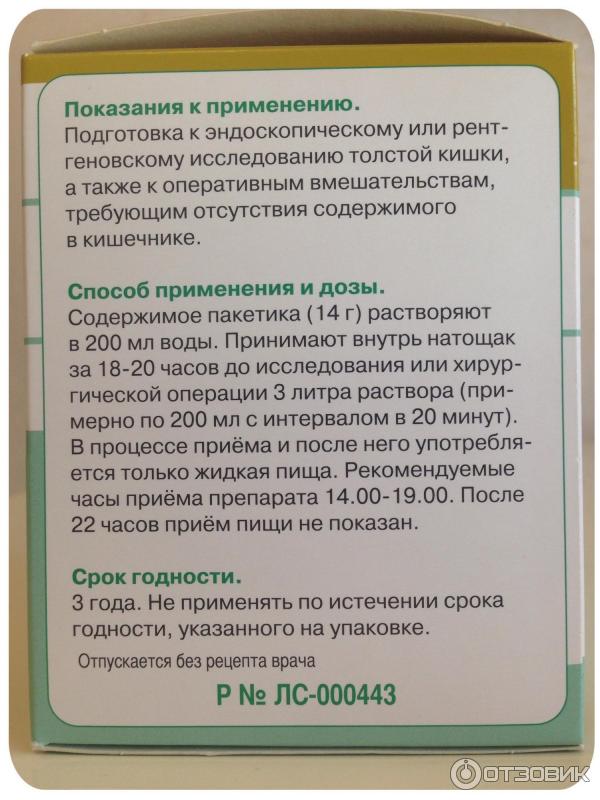

Подготовка к ирригоскопии: необходимые препараты